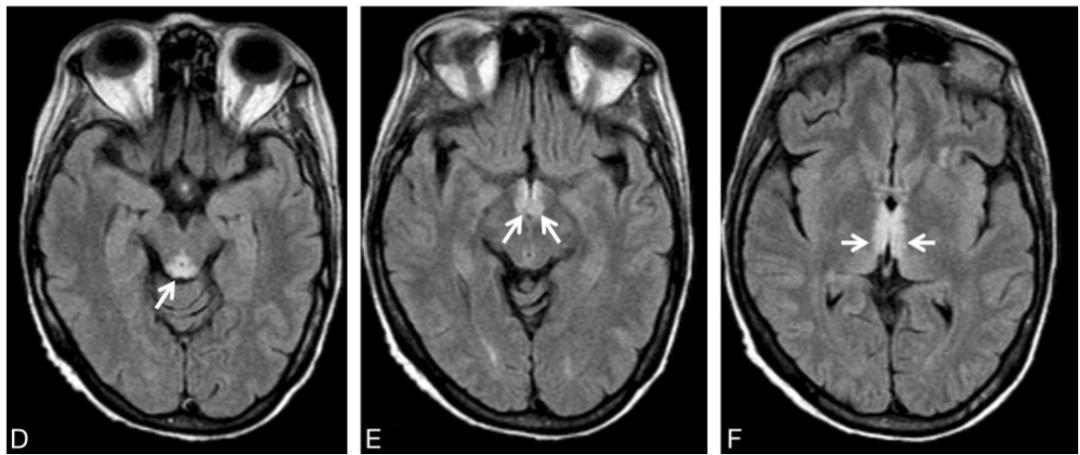

男,54歲,白血病病史。臨床表現(xiàn)為意識障礙、共濟失調。Flair示高信號位于雙側舌下神經(jīng)核(A)、前庭神經(jīng)內側核(B)、面神經(jīng)核(長箭頭)和展神經(jīng)核(短箭頭)(C)、中腦頂蓋和導水管周圍灰質(D)、乳頭體(E)、下丘腦和第三腦室周(F)。